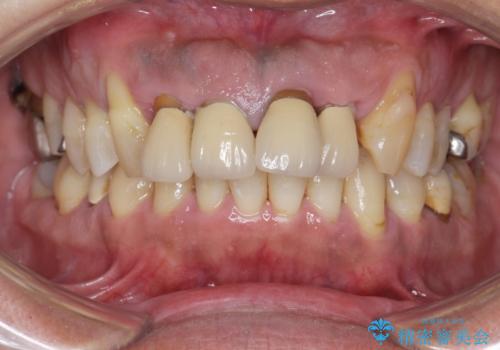

歯周病 、インプラント、 矯正 全顎治療

担当医 大元洋佑

歯周病治療の注意事項(リスク・副作用など)

- 外科手術のため、術後に痛みや腫れ、違和感を伴います

- 歯周組織再生治療は患者様の状態によって術後の経過が異なります(見た目が改善しない場合もあります)

- 歯周組織再生治療は自費診療(保険適用外)となります